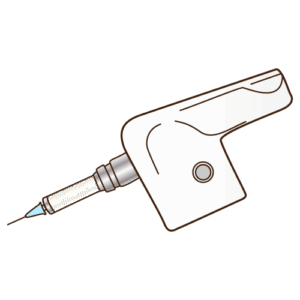

表面麻酔の徹底: いきなり注射針を刺すことはありません。必ず、注射する部位の歯肉にゼリー状の「表面麻酔薬」を塗布し、粘膜の感覚を麻痺させます。

極細の注射針の使用: 注射針は、細ければ細いほど痛みを感じにくくなります。当院では、現在日本で認可されている中で最も細いクラスの注射針を使用しています。

麻酔薬の温度管理: 麻酔薬が冷えていると、体内に注入されたときに「ヒヤッ」とした刺激や痛みを感じます。当院では、麻酔薬を体温に近い温度に保温する専用のウォーマーを使用しています。

非常にゆっくりとした注入: 痛みを感じる最大の原因は、麻酔薬を注入する「圧力」です。コンピューター制御の電動注射器を使用するか、あるいは熟練した手技により、麻酔薬が組織に染み込んでいくのを待つように、非常にゆっくりとしたスピードで注入します。